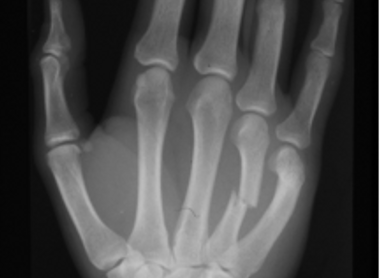

Hand and wrist fractures: The ‘SBCDS’ approach